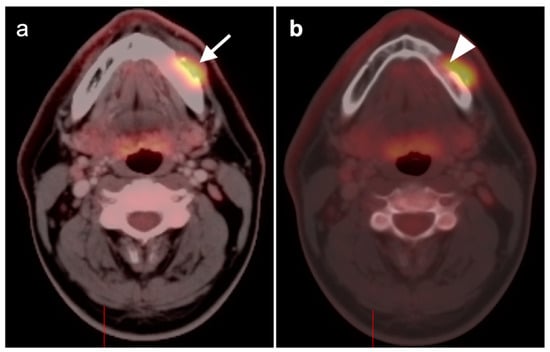

2.5. Major and Minor Salivary Gland, Lacrimal Gland Tumors

- Pleomorphic adenoma and carcinoma ex pleomorphic adenoma

- 2.

- Warthin tumor

- 3.

- Mucoepidermoid carcinoma

- 4.

- Adenoid cystic carcinoma

2.6. Thyroid Cancer